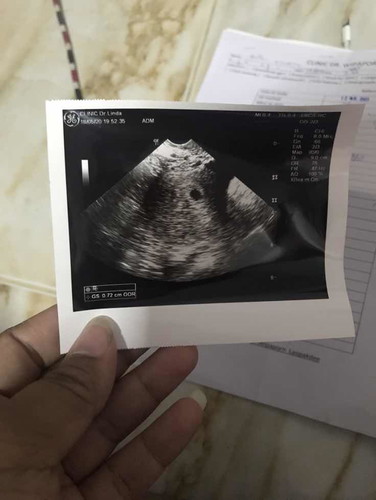

คือประจำเดือนมาครั้งสุดท้าย วันที่19มีนา63 แล้วหมดไปในวันที่23มีนา63 พอมาต้นเดือนพฤษภาลองตรวจครรภ์เอง ผลออกมา2ขีด แล้วพอดีพึ่งไปหาหมออัลตร้าซาวด์มาวันที่19พฤษภา ผลคือท้องที่โพรงมดลูก ขนาดถุงน้ำที่เจอยัง 7มิลอยู่เลย หมอเลยบอกยังพึ่งเดือนแรกอยู่เลย ...เลยอยากทราบว่าจะรู้ได้ไงค่ะว่าตอนนี้ท้องกี่สัปดาห์กันแน่ ตอนนี้เครียดมากเลยค่ะ